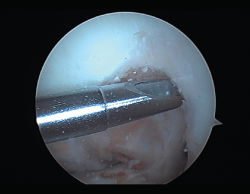

Figura 7. Adherencias intraarticulares.

Las principales causas secundarias a errores técnicos son la malposición de la plastia y el tensado excesivo. La radiografía permite ver la localización de los túneles e implantes, así como la RM visualiza las partes blandas implicadas, pudiendo identificar posibles pinzamientos de la plastia –escotadura intercondílea, síndrome del cíclope (Figura 9), síndrome de la contractura infrapatelar(22)(Figura 10)–.